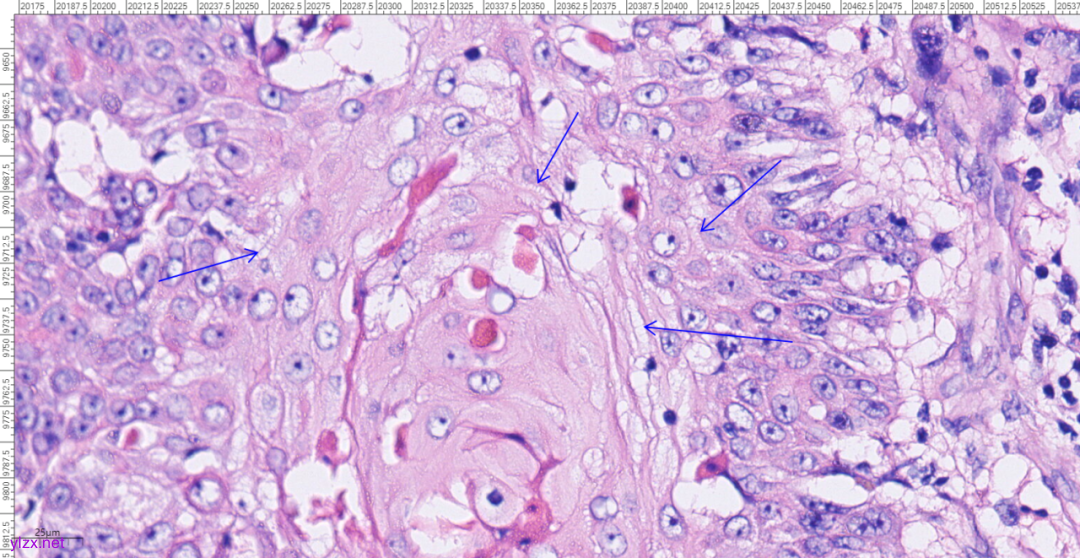

图5 局部囊壁表面可见由正常鳞状上皮-原位癌-鳞状细胞癌逐渐过渡。

图6 在SCC区域,癌巢向下浸润性生长,也向囊腔内乳头状生长。

图7 高倍镜下,癌巢中央可见角化珠。

图8 高倍镜下,高分化鳞癌细胞之间可见细胞间桥。

图9 高倍镜下,中分化鳞癌细胞呈空泡状,核仁明显,核分裂象易见。

镜下观:

MCT-SCC在形态学上分为MCT和鳞状细胞癌两种成分,其中MCT镜下可见由发育成分化良好的外胚层、内胚层和中胚层组织,如牙齿、头发、骨骼和皮脂腺。SCC镜下见增厚的囊壁处有鳞状细胞癌成分,表现为异型增生的鳞状上皮细胞突破基膜向间质延伸,增生的纤维结缔组织中见肿瘤细胞排列成巢状,细胞大小不等,排列紊乱,核分裂象易见;可见同心圆排列的角化珠。病理医师应对标本充分取材进一步提高其诊断水平。